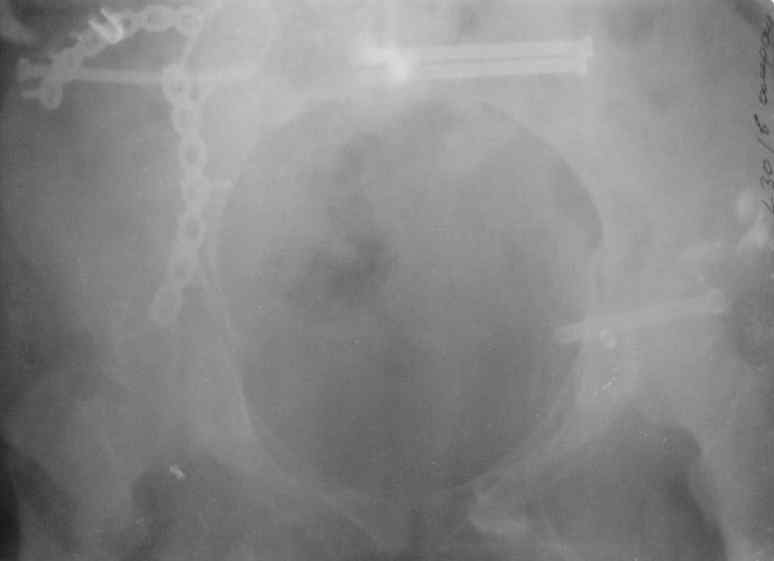

Молодая девушка 19 лет, травма 1 год назад, тогда же прооперирована.

В настоящее время имеются ноющие боли в области крестца слева, нарушение походки, ощущение неуверенности, слабости в левой нижней конечности, неврологически -непостоянные парестезии в левой нижней конечности. Ходит с дополнительной опорой, страдает от ожирения.

В приложении снимки при поступлении и послеоперационные год назад.

Могу сказать одно: миграция винтов и нестабильность синтеза левого подвздошно-крестцовогоо сочленения очевидна.